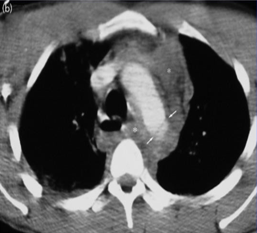

胸片 仰卧位 supine trauma patient ![]() 1. 上纵膈增宽 superior mediastinal outline widening 2. 支气管移位 tracheal deviation

3. 左侧支气管移位 displacement left bronchus

4. 主肺动脉窗消失 obliteration of aorto- pulmonary window.